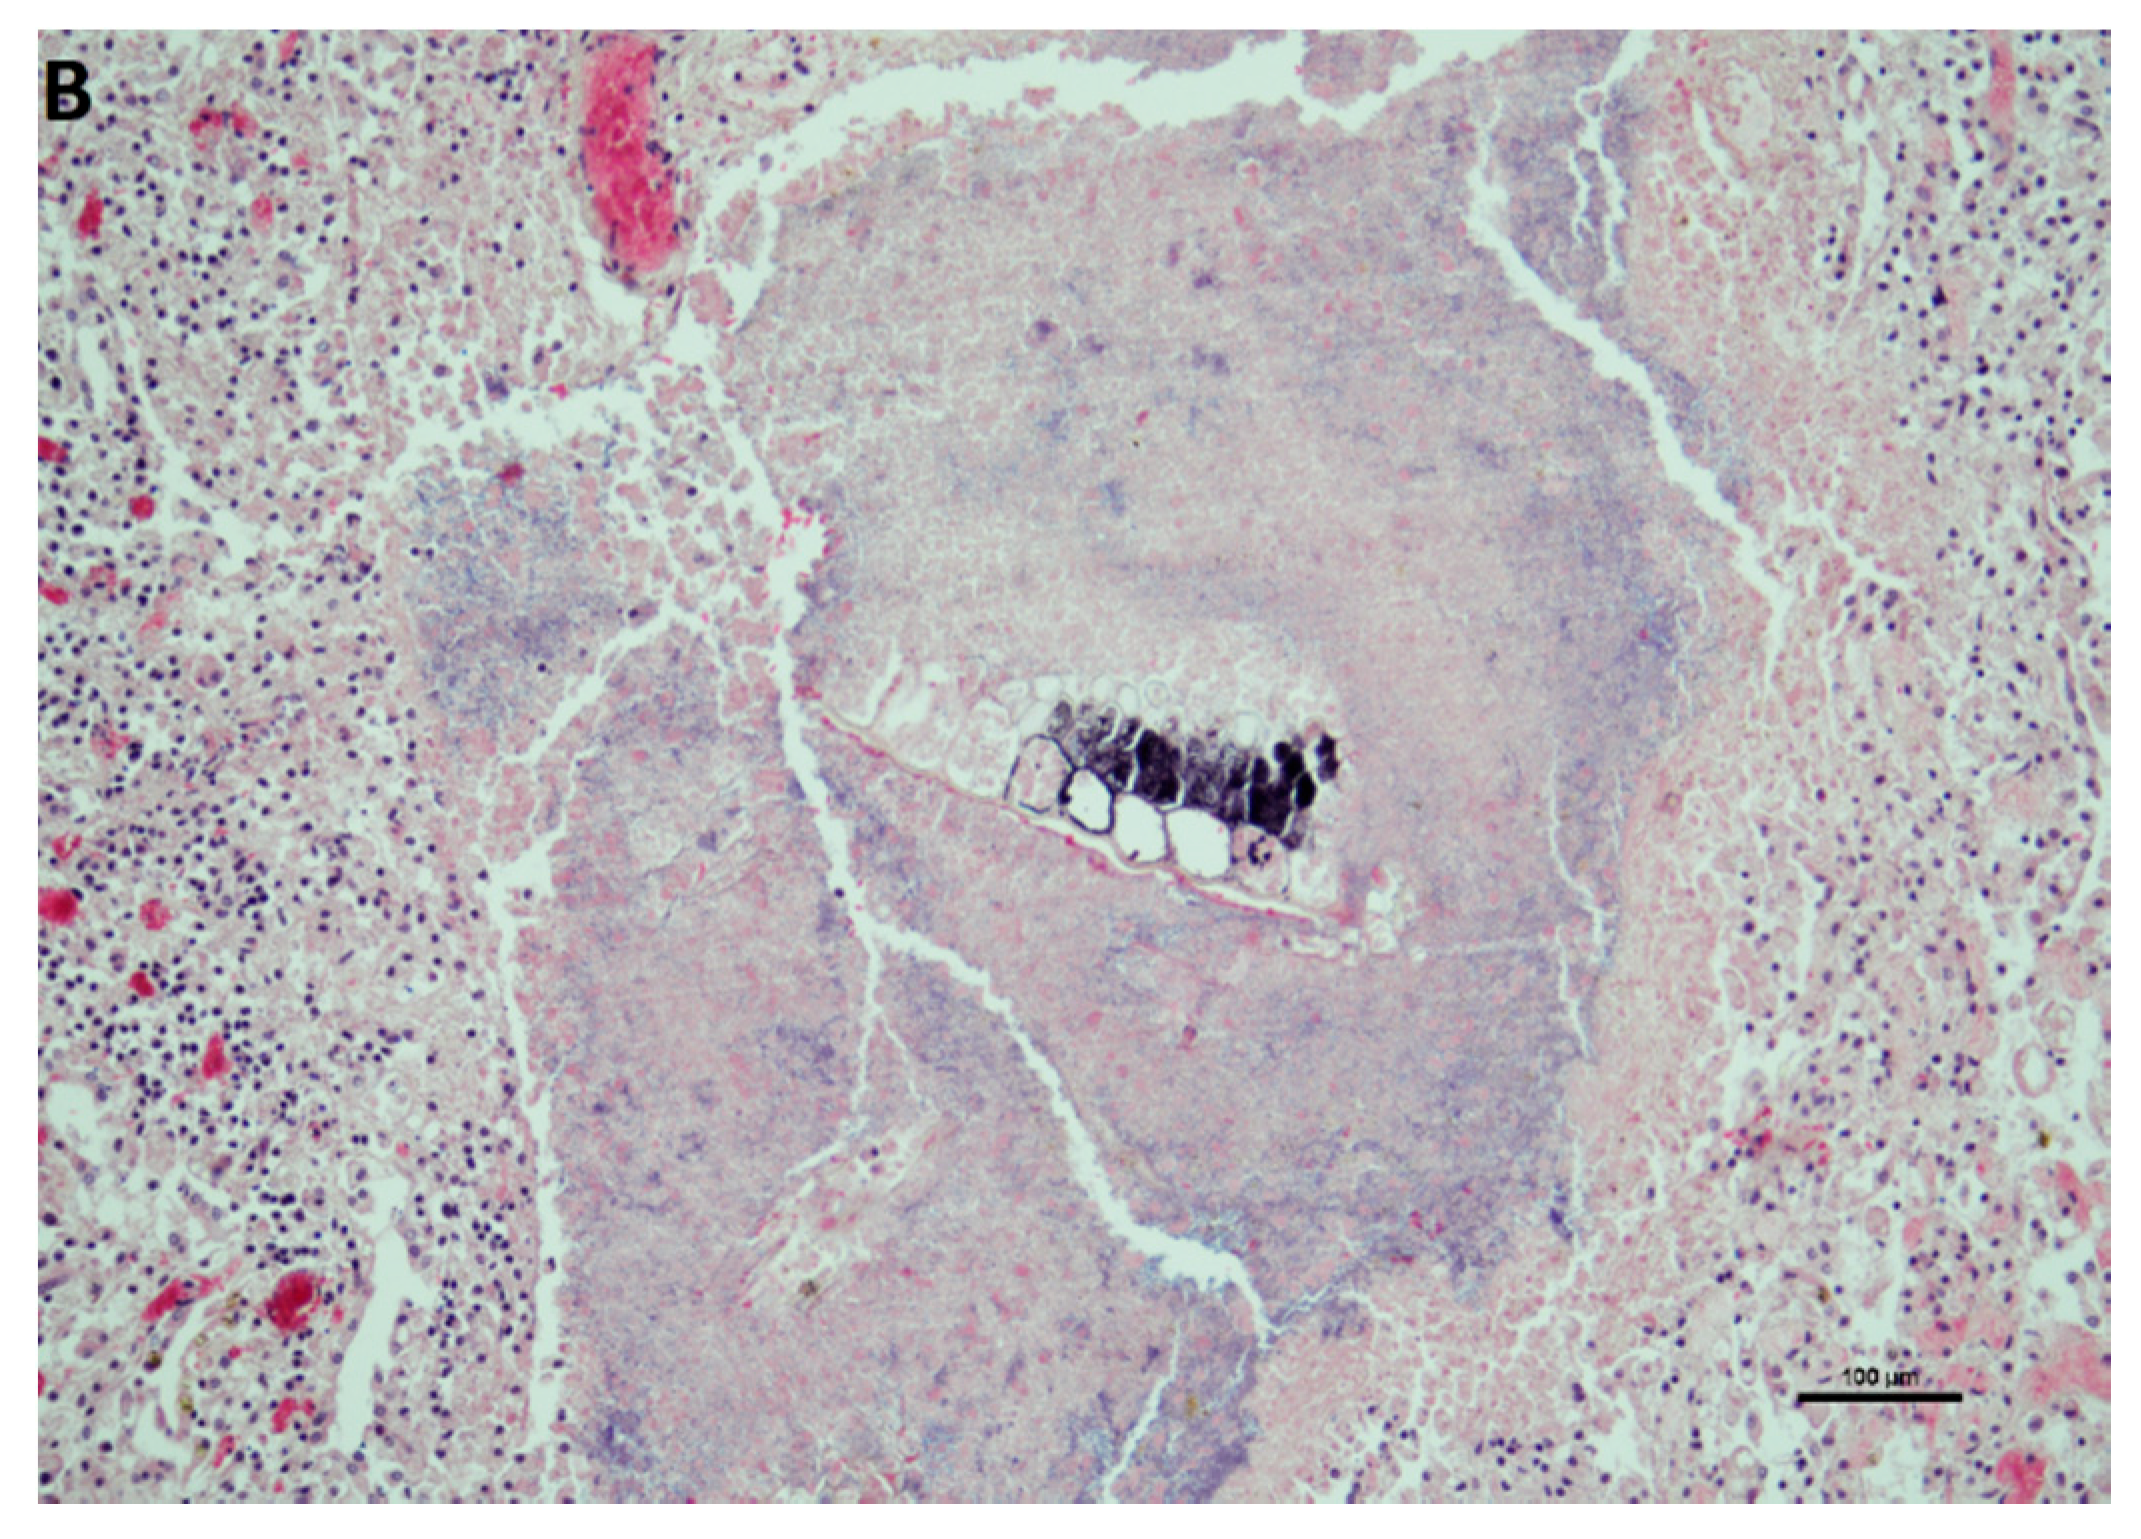

3.1. Postmortem Examination